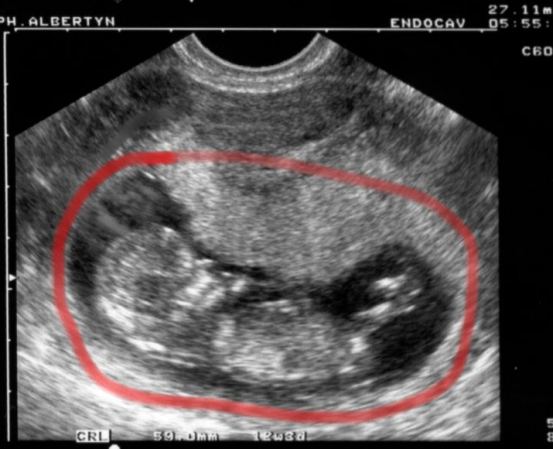

27th November

12.5 Weeks. A side view. On the left you see the head. In video you would see arms and hands waving about. It's all quite impressive to me. We've measured the thickness of the neural chord between the head and body as an indication of nervous system development and to rule out any birth defects in this area. And none to our surprise but to our relief nevertheless, all is well.